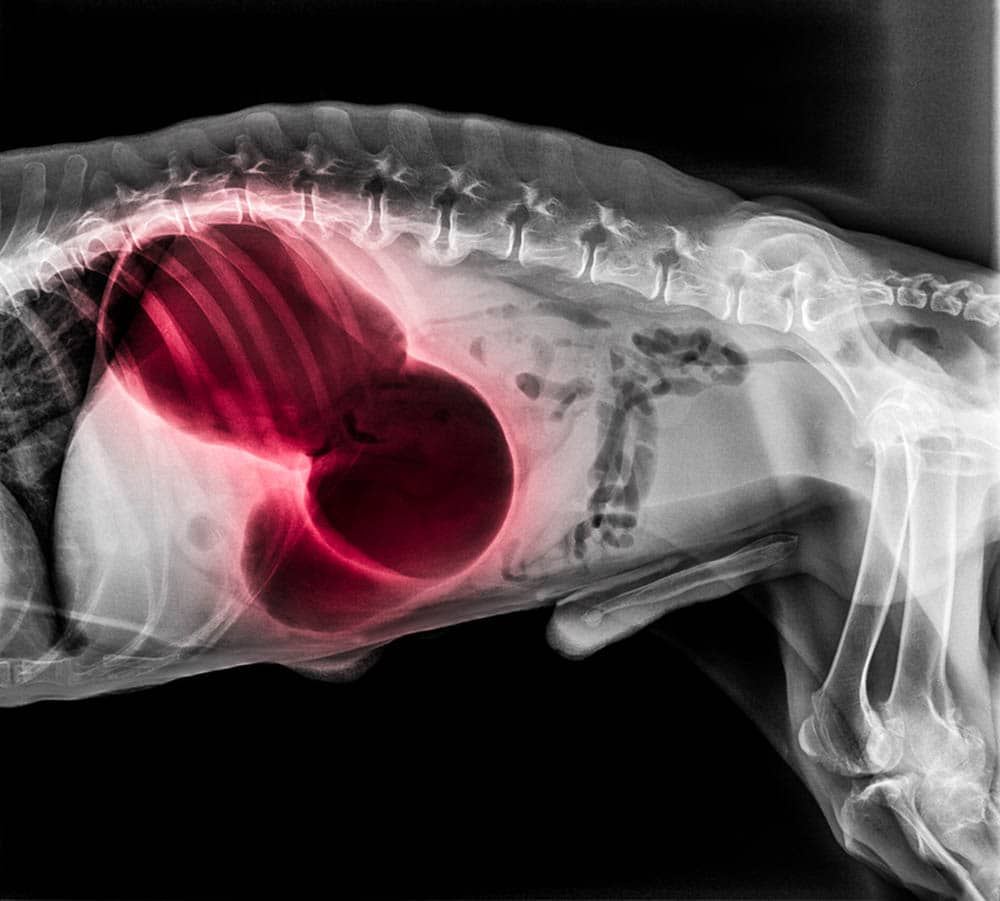

1. Gastric Dilation Volvulus

Gastric dilation volvulus (GDV), or bloat, is a serious and often fatal condition that occurs when gas or food stretches a dog’s stomach. The bloated stomach then rotates, trapping the gas inside and prohibiting blood flow. The gas continues to build up, and if left untreated, GDV can take your dog’s life within a few short hours.

X-ray of dog lateral view red highlight in Gastric dilatation volvulus

Image By: Intarapong, Shutterstock